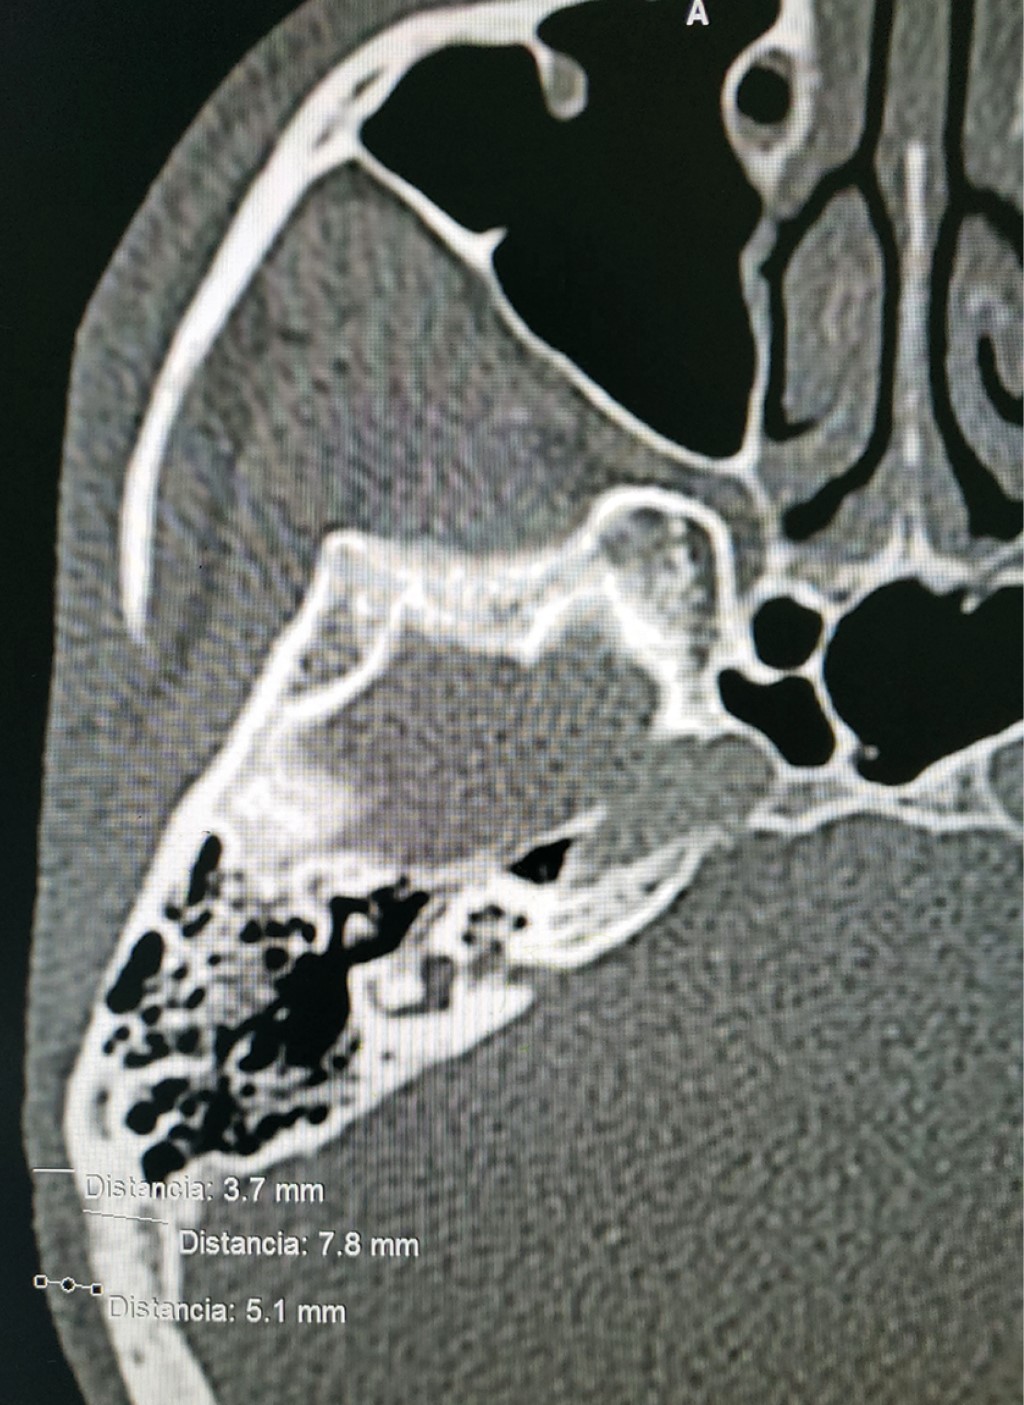

Paciente masculino de 26 años de edad, asiste a consulta de cirugía maxilofacial por fracaso en cirugía de reconstrucción auricular con injerto costocondral, se realizó la historia clínica completa del paciente el cual refiere "inconformidad estética". En el examen clínico se observa microtia en pabellón auricular derecho grado III de Marx (Figura 1) en donde se aprecia un esbozo de cartílago amorfo. Se registró la medida del pabellón auricular contralateral para determinar la medida de la prótesis, dando un total de 62 mm, esto con el fin de tener un resultado armónico y simétrico, Se comenzó con la planeación quirúrgica y se analizó detalladamente la tomografía para evaluar el espacio disponible para los implantes; se registraron medidas de hueso disponible en los distintos cortes tomográficos (Figura 2), así como de tejido blando, lo que permite seleccionar el pilar implantológico adecuado para el caso. Se realizó un modelo estereolitográfico en donde se midió el área disponible para la colocación de implantes; en este caso se planeó la colocación de tres implantes a 13 mm de distancia del conducto auditivo externo (CAE): posteriormente se realizó la cirugía en el modelo estereolitográfico (Figura 3) para poder analizar el resultado y se fabricó una guía para la colocación de implantes que permitiera posicionarlos a las 7, a las 9 y a las 11, a 13 mm de distancia del CAE. En el acto quirúrgico se realizó una incisión retroauricular hecha a 50 mm del CAE para exponer la porción mastoidea del hueso temporal en donde se colocó la guía quirúrgica (Figura 4). Se realizó el protocolo de fresado para implantes 4.1 × 6 mm (Figura 5) y se insertaron los implantes en su posición, a un torque final mínimo de 45 nm (Figura 6) se colocaron los tornillos tapa de los implantes y, por último, se remodeló el cartílago preexistente y se suturó el lecho quirúrgico con nylon 5-0 (Figura 7). Se llevó un control postoperatorio durante los siguientes cuatro meses para evaluar la completa osteointegración de los implantes.

Figura 2